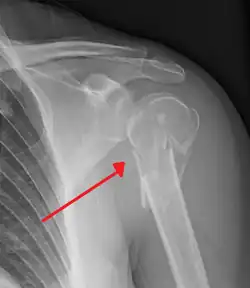

Proximal humerus fracture -